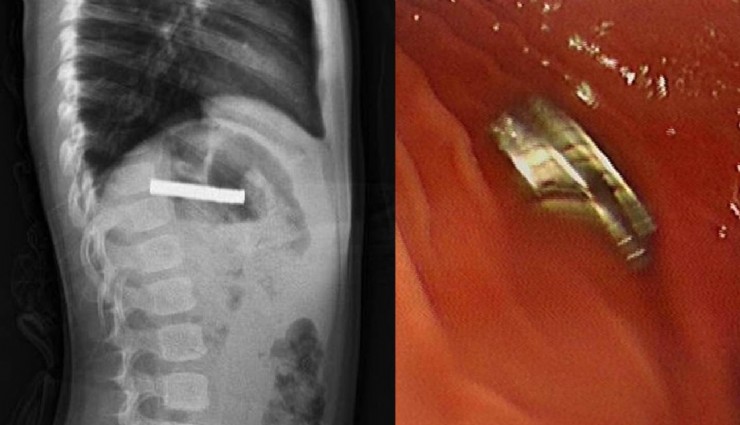

Elazığ’da 3 yaşındaki bir çocuğun yuttuğu 19 mıknatıs, Fırat Üniversitesi Hastanesinde başarılı bir operasyon ile çıkartıldı.

Edinilen bilgiye göre, Erzurum’da bir çocuk evde bulunan 19 tane mıknatısı yuttu. Çocuğun rahatsızlanması sonucu durumu öğrenen aile hastaneye başvurdu. Daha sonra çocuk Elazığ’a sevk edildi.

Fırat Üniversitesi Çocuk Gastroenteroloji Hepatoloji ve Beslenme Bilim Dalı Başkanı Prof. Dr. Yaşar Doğan, çocuk hastanın yemek borusuna yapışmış 19 mıknatısı endoskopik yöntemle çıkardı.

Mıknatıslar uzun süre yemek borusunda takılı kaldığı için yemek borusu ve mide girişinde zedelenmeler olurken, çocuğun sağlık durumunun iyi olduğu ve taburcu edildiği öğrenildi.